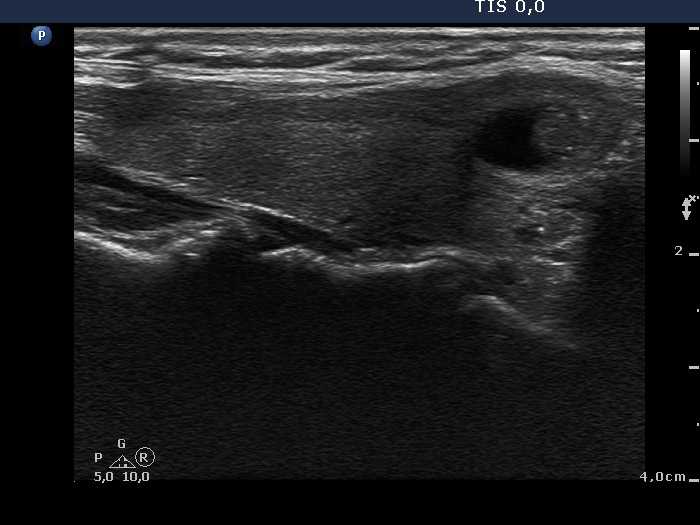

Initial examination (1st and 2nd rows of images):

Clinical presentation: a 50-year-old woman was referred for an evaluation of neck pain localized to the right thyroid and fever.

Palpation: the right thyroid was painful and hard.

Laboratory examination: hyperthyroidism (TSH 0.01 mIU/L, FT4 43.4 pM/L), CRP 18.3 mg/L.

Ultrasonography: there were multiple hypoechogenic areas with ill-defined borders in both lobes, primarily in the right one. The vascularization was decreased.